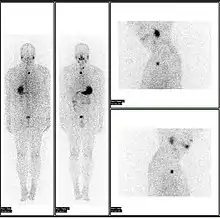

![]() A nuclear medicine PET scan | |

Normal whole body PET/CT scan with FDG-18. The whole body PET/CT scan is commonly used in the detection, staging and follow-up of various cancers.

Abnormal whole body PET/CT scan with multiple metastases from a cancer. The whole body PET/CT scan has become an important tool in the evaluation of cancer.